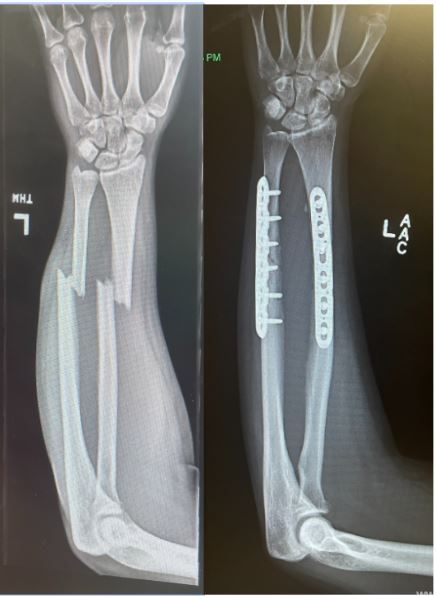

A drug-eluting plate or coated plate that inhibits bone growth selectively on the outer side, so that the plate would essentially stay on the outside of the bone rather than become submerged into the core as new bone grows and heals. Therefore, in the case where the plate would need to be removed, it would be easily accessible.